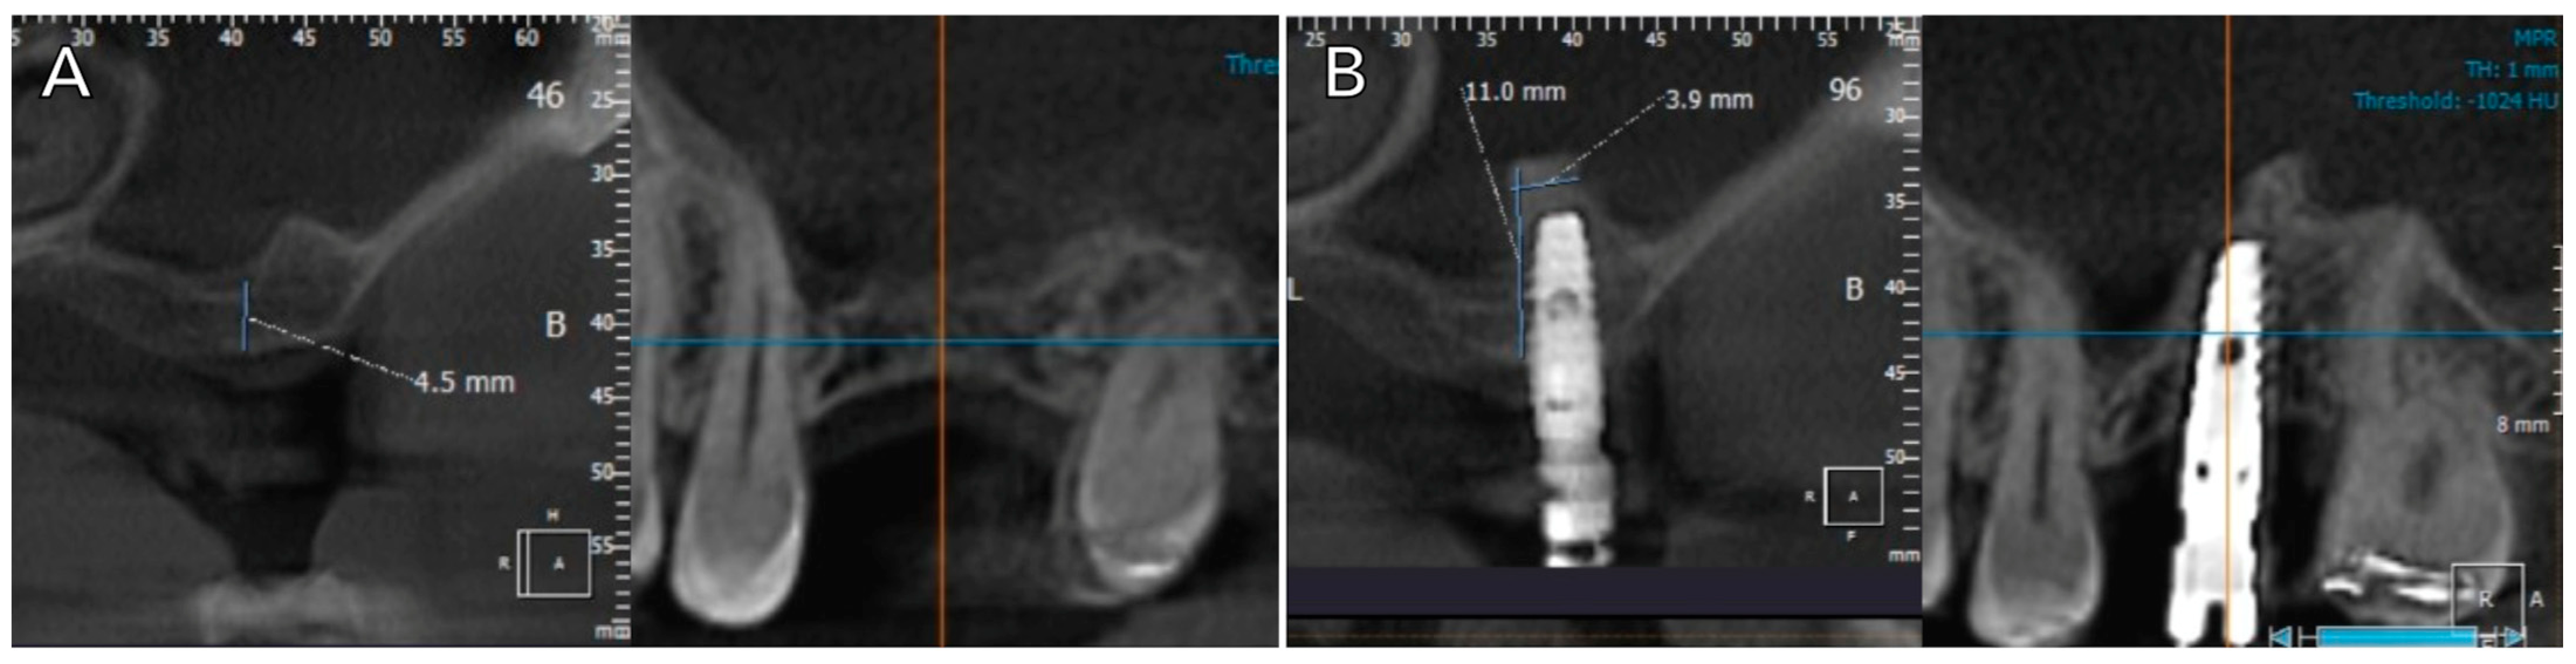

2.2. Clinical Protocol